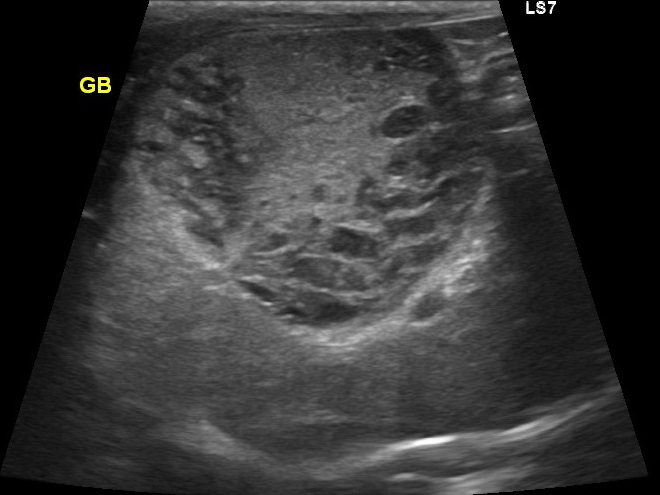

エコー検査では胆嚢の中を満たすほど胆泥が溜まっています。

エコーで胆嚢炎と胆嚢粘液嚢腫であることを確認し、破裂の危険性を考えて腹腔鏡下胆嚢摘出術を実施することになりました。